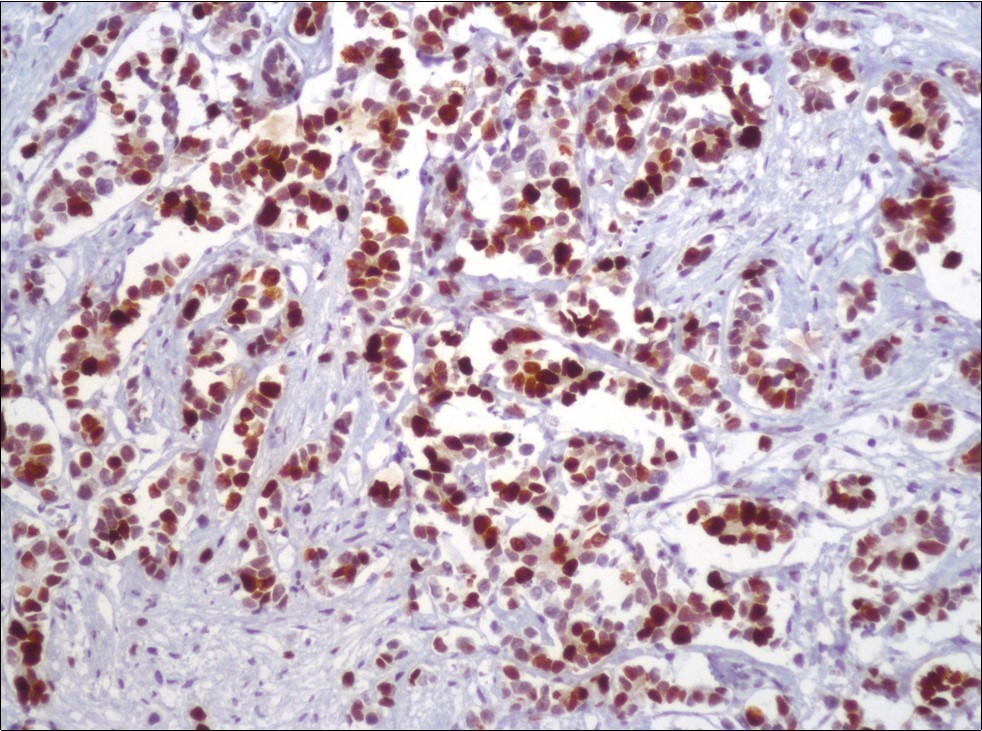

A 73-year-old male patient was admitted to our outpatient clinic with acute urinary retention. Digital rectal examination was normal. The PSA value was 1.81 ng/dl. Prostate size was 101 cc. Since the PSA value and digital rectal examination were normal, no biopsy was taken. Ultrasonography showed bilaterally ureterohydronephrosis. The creatinine level was 2.89 mg/dl. Hypertension has been presented as a comorbidity. An 18 Fr Foley catheter was inserted and alpha-blockers and 5-α reductase inhibitor medication was given. Creatinine level decreased to 0.91 mg/dl after one week. When the patient's catheter was pulled out, he could not urinate again. A catheter was inserted and waited one week more. After one week, the patient was unable to urinate again. The operation was decided due to this recurrent urinary retention. Because of prostate size was 101 cc and prostatic urethra was long, open prostatectomy was decided. When the prostate was removed during the operation, it was evaluated that the left side and the lower side were adhered to surrounding tissue. The prostate was removed as an en bloc. The catheter was removed after 5 days. The pathology of the patient has been reported as pure small cell prostate carcinoma. On the microscopic examination, the tumor was heavily infiltrated into the prostate parenchyma (Figure 1). Tumor cells were consist of atypical small-medium sized, mitotically active cells with a high nuclear to cytoplasmic ratio, hyperchromatic nucleus, nuclear molding, and inconspicuous nucleoli (Figure 2). On the immunohistochemically examination of synaptophysin showed diffusely and strong positivity while chromogranin A showed focal weak positivity with the absence of staining for PSA (Figure 3). Ki67 proliferative index was equal to 90% of the tumor cells (Figure 4). The results confirmed the diagnosis of prostatic small cell carcinoma. Metastatic lymph nodes were detected in the right perirectal region with metastatic multiple lymph nodes in the bilateral external iliac region, more on the left than in the PET CT. No metastasis was detected in the brain MRI and thorax computed tomography. Four cycles of etoposide and cisplatin chemotherapy were administered to the patient. Control PET CT taken after chemotherapy showed a significant decrease in size and metabolic activity of the right obturator and lymph nodes in the right perirectal area. The size and metabolic character of the left obturator, left external iliac and common iliac lymph nodes were increased. After a month, patient admitted to emergency outpatient clinic with left flank pain. There was an 8-cm mass in retroperitoneal area in the computed tomography. Supportive treatment was started because the patient could not tolerate chemotherapy. The masses reached to 13x11cm and fulfilled the retroperitoneal area. Multiple lung metastases were seen. The patient died 13 months later after the first diagnosis.

Figure 1.Infiltration of the tumor cells between prostatic ducts (H&E, x40)